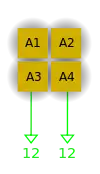

- The reconstruction process is illustrated in Figure 7.15.12 for a simple image consisting of a 2x2 pixel matrix. It starts with a guess of a solution and then compares the actual projections with the ones obtained on the basis of the guess. Modifications are made to the pixel values and the procedure is repeated. Repetitive iterations are made until the differences between the measured and calculated projections are insignificant.

- The first estimate of the image matrix is made by distributing the first projection, P1, evenly through an empty pixel matrix. The second projection, P2, is then compared to the same projection from the estimated matrix and the difference between actual and estimated projections is added to the estimated matrix. The process is repeated for all other projections.